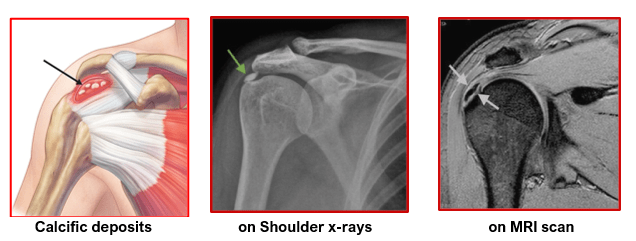

석회성 건염은 어깨 힘줄에 칼슘(석회)이 쌓여 극심한 통증을 유발하는 질환입니다. 40~60대에서 가장 흔하게 발생하며, 어깨를 자주 쓰는 직업을 가진 분들이 특히 주의해야 합니다.

석회성 건염은 힘줄 내부에 석회(칼슘 결정)가 침착되어 염증이 생기는 질환입니다. 초기에는 별다른 증상이 없다가, 갑자기 극심한 통증으로 나타나기도 합니다. 특히 밤에 통증이 심해져 잠을 제대로 이루지 못하는 경우가 많습니다.

• 엑스레이 촬영 시 하얀색 석회 덩어리가 관찰됨